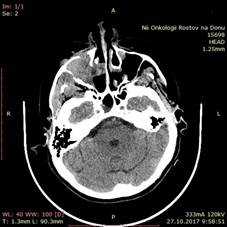

Больная Ж., 1957 года рождения, поступила в отделение ОГШ ФГБУ «РНИОИ» МЗ РФ 10.11.2017 г. с жалобами на затрудненное носовое дыхание через правую половину носа, кровотечения из правой половины носа. Из анамнеза: считает себя больной с ноября 2016 г., когда периодически отмечала кровотечения из правой половины носа. Обращалась к врачу по месту жительства, однако консервативное лечение, проводимое по месту жительства, осталось без эффекта. В марте 2017 г. по поводу зубной боли обратилась к стоматологу, где лечилась по поводу лакунарной кисты. В конце марта 2017 г. возникло кровотечение из правой половины носа. По месту жительства 10.04.2017 г. выполнялось прижигание сосудов слизистой оболочки полости носа справа. 10.05.2017 г. возобновилась кровоточивость с последующим носовым кровотечением. В ГБУ РО РОКБ 06.07.2017 г. выполнена операция: правосторонняя гайморотомия, этмоидотомия, удаление новообразования правой половины носа с использованием видеоэндоскопических технологий. Послеоперационный гистологический анализ № 57554-61 - кавернозная гемангиома. Больная была выписана в удовлетворительном состоянии с восстановленным носовым дыханием, кровотечение из правой половины носа прекратились. Через 1 неделю возобновились носовые кровотечения из правой половины носа, была направлена в ЛОР-отделение ГБУ РОКБ, где 18.08.2017 г. выполнена операция - правосторонняя гайморотомия комбинированным доступом (ревизия по Дэнкеру) с использованием видеоэндоскопических технологий, обезболивание общее. Послеоперационный гистологический анализ № 70827-30 от 25.08.2017 г. (ИГХ) меланома. Наблюдалась по месту жительства. Однако носовые кровотечения не прекратились, что побудило больную обратиться в ФГБУ «РНИОИ» МЗ РФ, где были пересмотрены гистологические препараты. Выполнены СРКТ околоносовых пазух и МРТ сосудов головного мозга. При осмотре специалиста в профильном кабинете клинико-диагностического отделения ФГБУ «РНИОИ» МЗ РФ: лимфатические узлы шеи не пальпируются. Лицо асимметричное за счет распространения опухоли в мягкие ткани правой щеки. Пальпаторно - костные края орбиты не изменены. При орофарингоскопии - открывание полости рта в полном объеме. При передней риноскопии - в общем носовом ходе справа гнойно-геморрагические корки, опухоль не определяется при осмотре. СРКТ от 27.10.2017 г. - опухоль правой верхнечелюстной пазухи 3,8х3,9х3,3 см с разрушением ее передней, задней стенок, распространением в мягкие ткани щеки и правый общий носовой ход; легочная ткань без очагов; патологических объемных образований в брюшной полости и полости малого таза не выявлено (рис. 3).

Рис. 3. СРКТ придаточных пазух носа: справа - опухоль правой верхнечелюстной пазухи 3,8х3,9х3,3 см с разрушением ее передней, задней стенок, распространением в мягкие ткани щеки и правый общий носовой ход